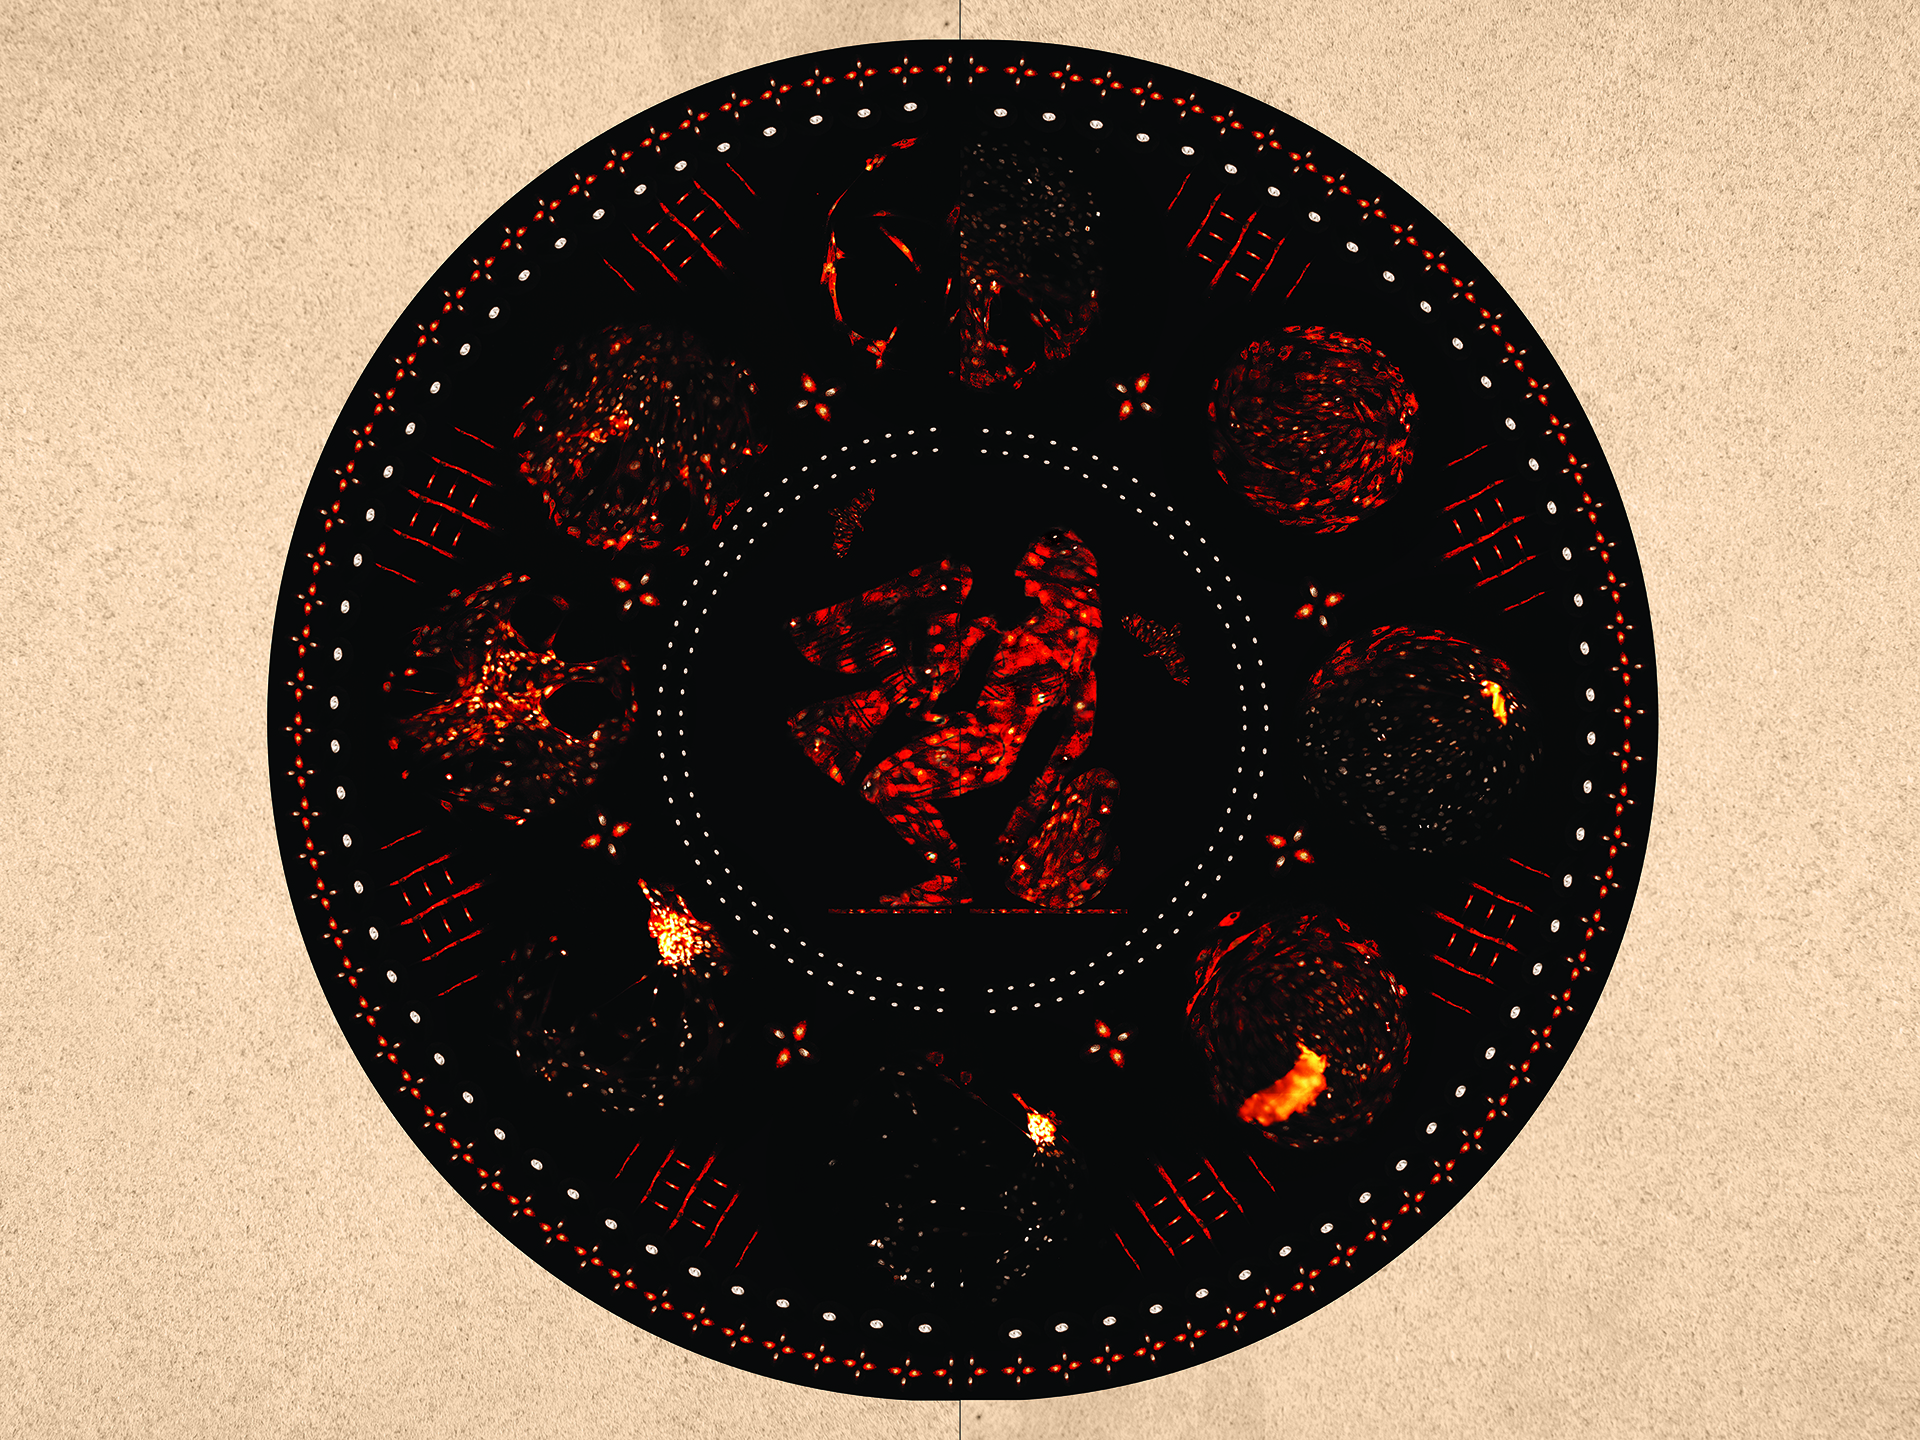

The liver is a remarkable organ that deactivates toxins, aids in the digestive process, and can regenerate after a loss of as much as 75 percent of its tissue. Liver fibrosis is a condition in which liver tissue is chronically inflamed, resulting in scarring that can lead to liver cancer or liver failure. Researchers are studying the growth pattern of liver cells in different microenvironments to understand how to better treat this condition.

In this image, liver cell growth patterns were used to recreate the myth of Prometheus in the style of a Greek Laconian vase painting. As a punishment for bringing the innovation of fire to humankind, Prometheus was held captive as his liver was consumed by an eagle each day, recovering each night only to be consumed once again. This image draws a line between a knowledge of bodies that stretches back millennia and the modern scientific goal to convert suffering to healing.